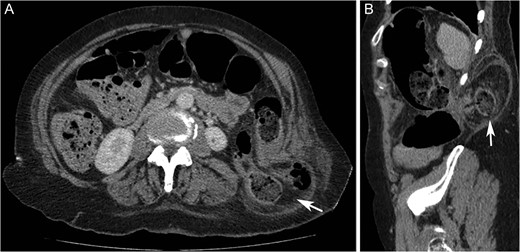

On examination, there was a 15 cm, irreducible, mildly tender lump in the left superior lumbar triangle, in the region of previous lipoma excision. There were audible bowel sounds on auscultation of the lump. No other swellings of the abdominal wall were identified and the patient was not known to have any hernias. Abdominal radiograph revealed faecal loading in the ascending colon with dilated large bowel loops (Fig. 2). Subsequent computed tomography (CT) scan showed a left superior lumbar triangle hernia containing a loop of colon (Fig. 3) with dilated large bowel proximal to this, in keeping with obstruction.

Computed tomography axial (A) and sagittal (B) images showing left sided superior lumbar triangle (Grynfeltt-Lesshaft) hernia containing loop of (‘arrows’) in a 72-year-old woman.

At emergency laparotomy a left-sided lumbar hernia with 2 × 3 cm defect was confirmed, containing necrotic omentum and a loop of descending colon. The left colon was mobilized lateral to medial and the hernia was reduced with external pressure by an assistant. Necrotic omentum was excised but the reduced bowel appeared healthy with no resection required. A retroperitoneal space was created and the hernia defect was repaired with 9 × 6 cm Prolene mesh placed in the plane between the opened peritoneum and the muscle. As it was not possible to completely close the peritoneum over the repair, a tongue of omentum was fixed between the repair and the descending colon.